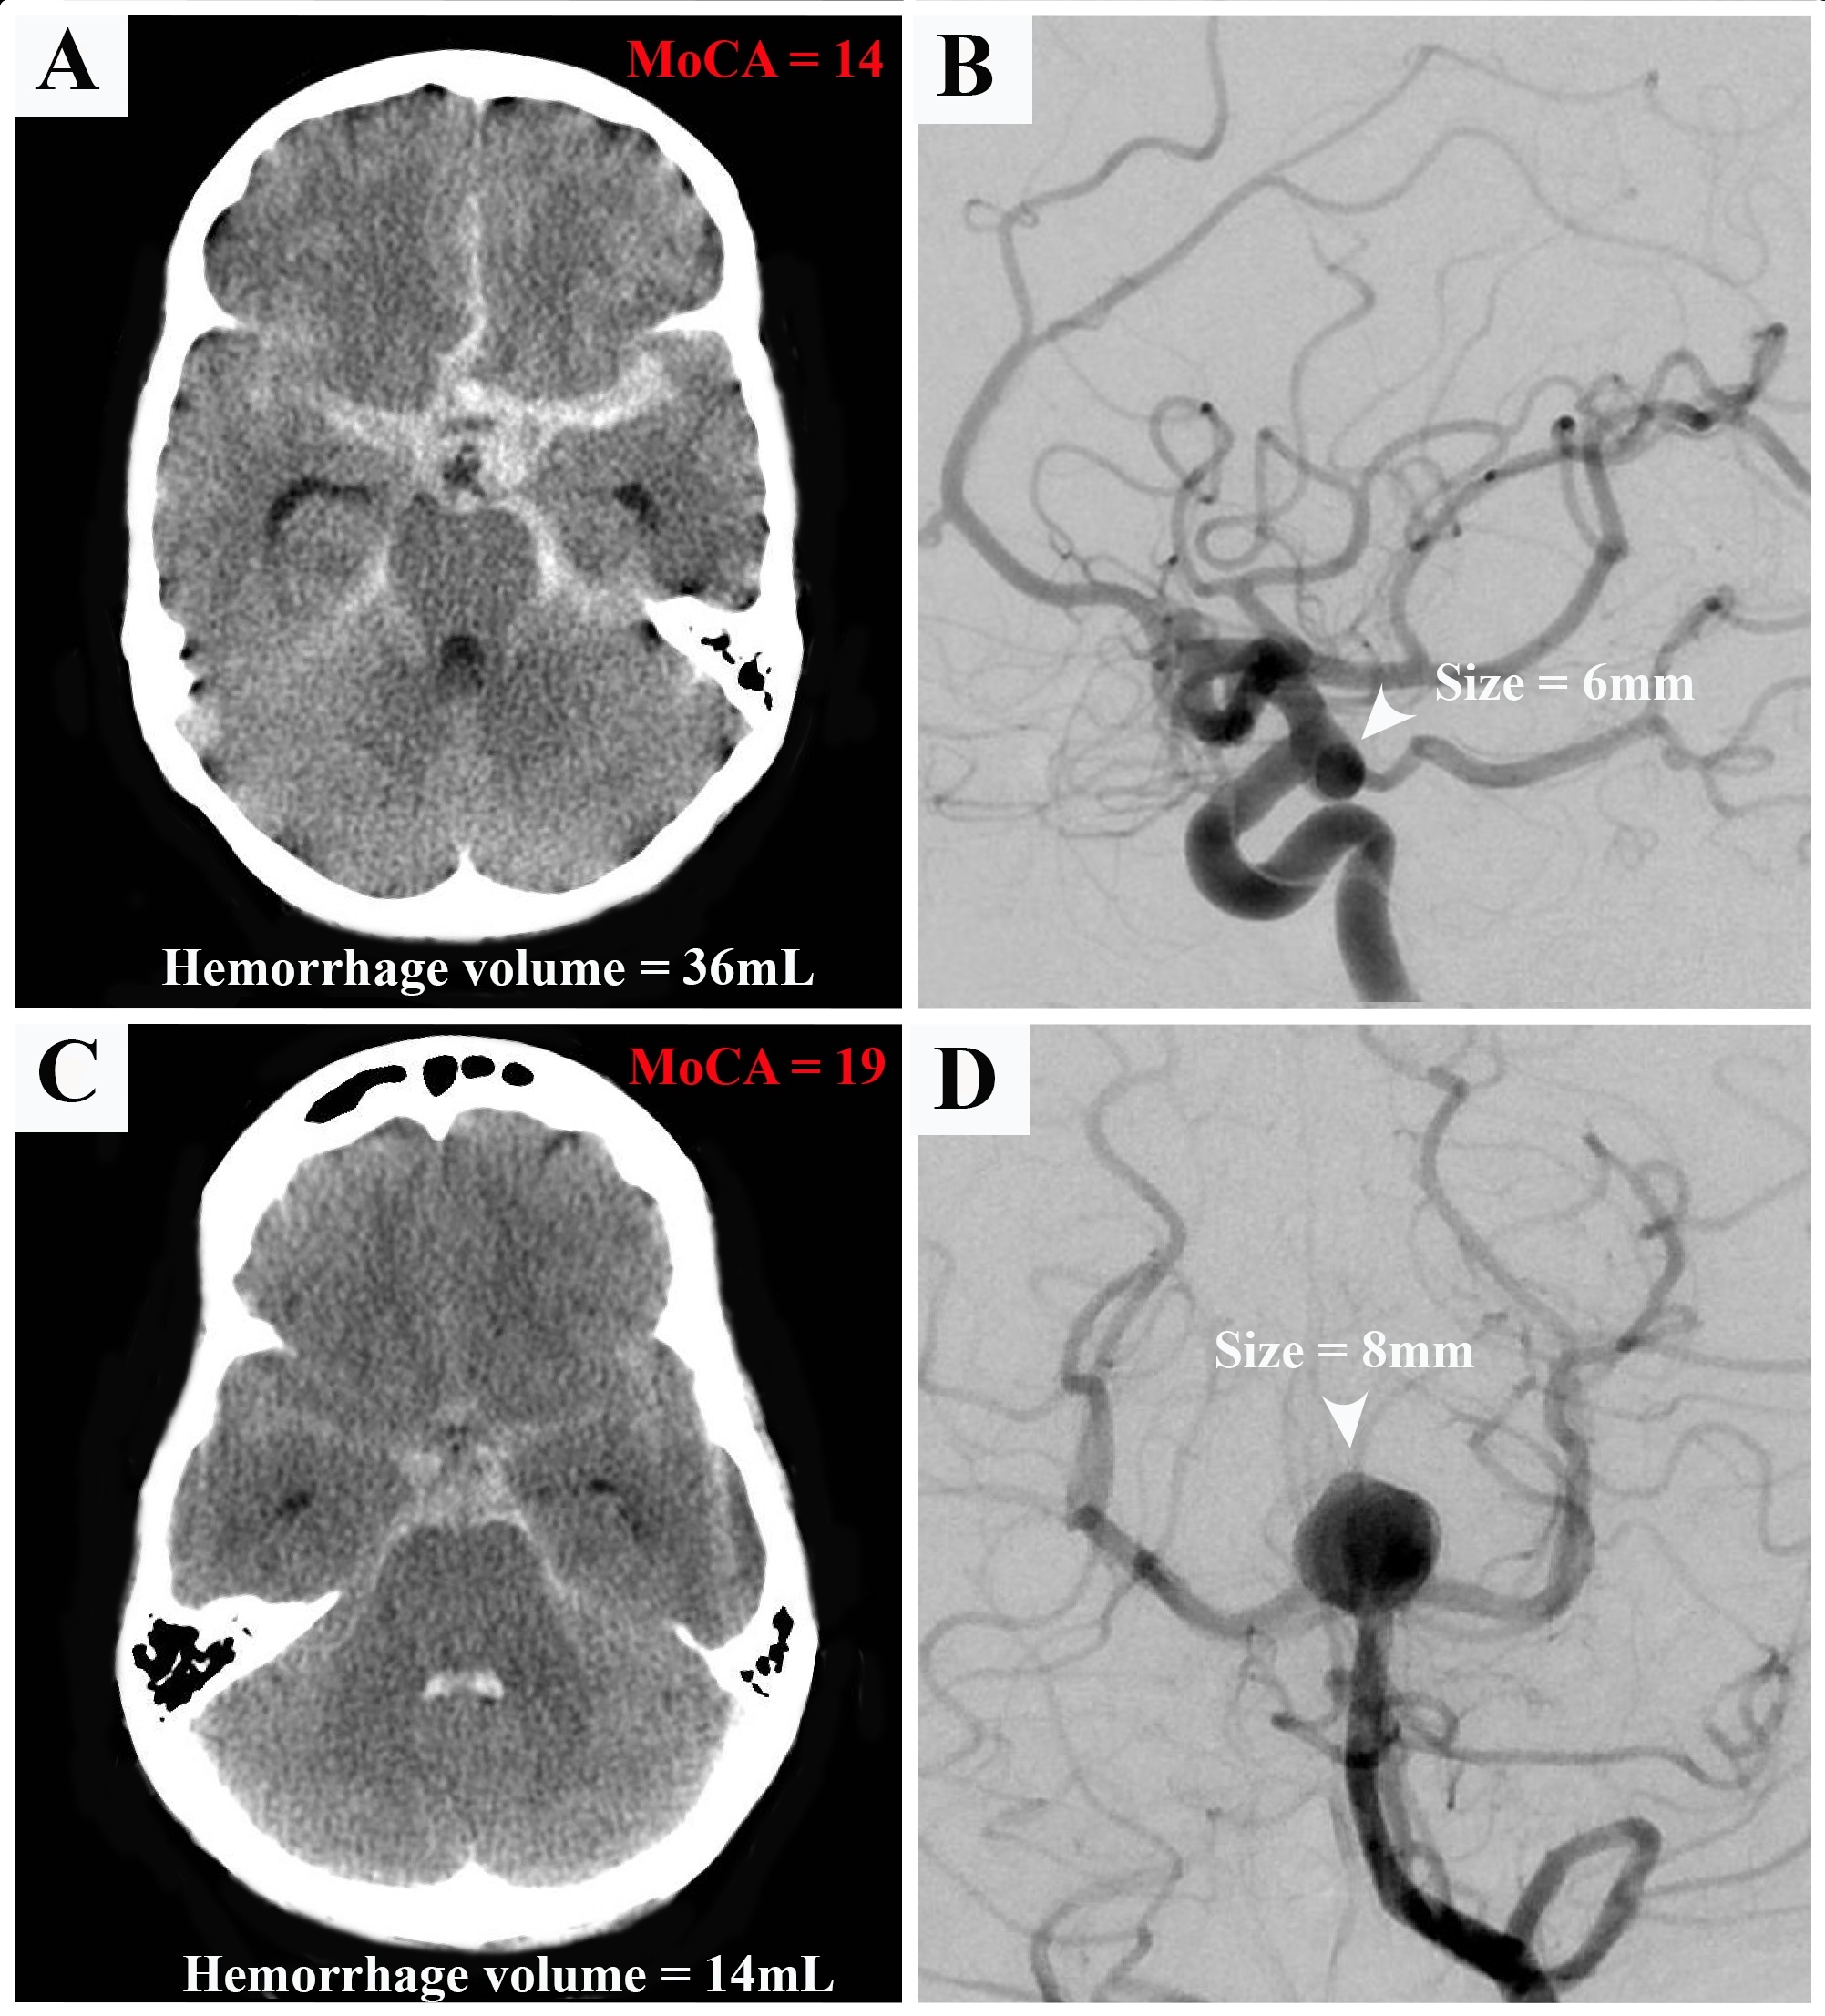

A total of 165 aSAH survivors were enrolled in the study. Short (32/165 patients) - and long-term outcomes (127/165 patients) were analyzed (3-12 months and 1 to 15 years post-aSAH respectively). In the short term, MoCA was significantly worse (<25th percentile for adjusted data, p 0.003) in patients with high mRS at discharge (median 3, IQR 2) compared to low mRS (median 1, IQR 2, OR:2.14, p 0.006). In the long term, MoCA was significantly worse in patients with higher Hunt and Hess (OR: 1.39, p 0.09), higher modified Fisher grades (OR: 1.29, p 0.1) and in patients who developed new radiological ischemia during hospitalization (OR: 3.42, p 0.03). Larger total hemorrhage volumes were significantly correlated with worse MoCA performance (β: 0.97, p=0.048, figure). Radiological vasospasm (β: -0.40, p 0.006), new ischemia (β: -0.37, p 0.012), and higher Hunt and Hess grades (β: -0.30, p 0.053) were identified as predictors of poorer quality of life. Additionally, lack of stamina and executive personality changes were among the most frequently reported changes by family members post-aSAH for patients.